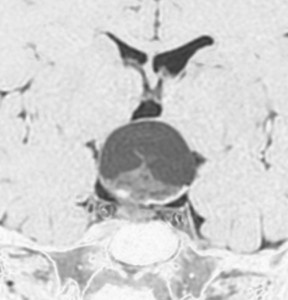

鞍隔膜上 supradiaphragmic type

この子の症状は頭痛だけ。両親はなぜ気づかなかったのかと疑問を持ちますが,巨大になるまで症状が出ないこともあるのです。左のCTで腫瘍の周囲にバラバラと白い点状の石灰化があるので診断できます。左の視床下部から発生したクラニオでした。開頭手術しますが超高難易度です,怖いです (┯_┯) 複数回開頭手術になりましたが結果的に全摘出できています (by Dr 山本哲哉)。